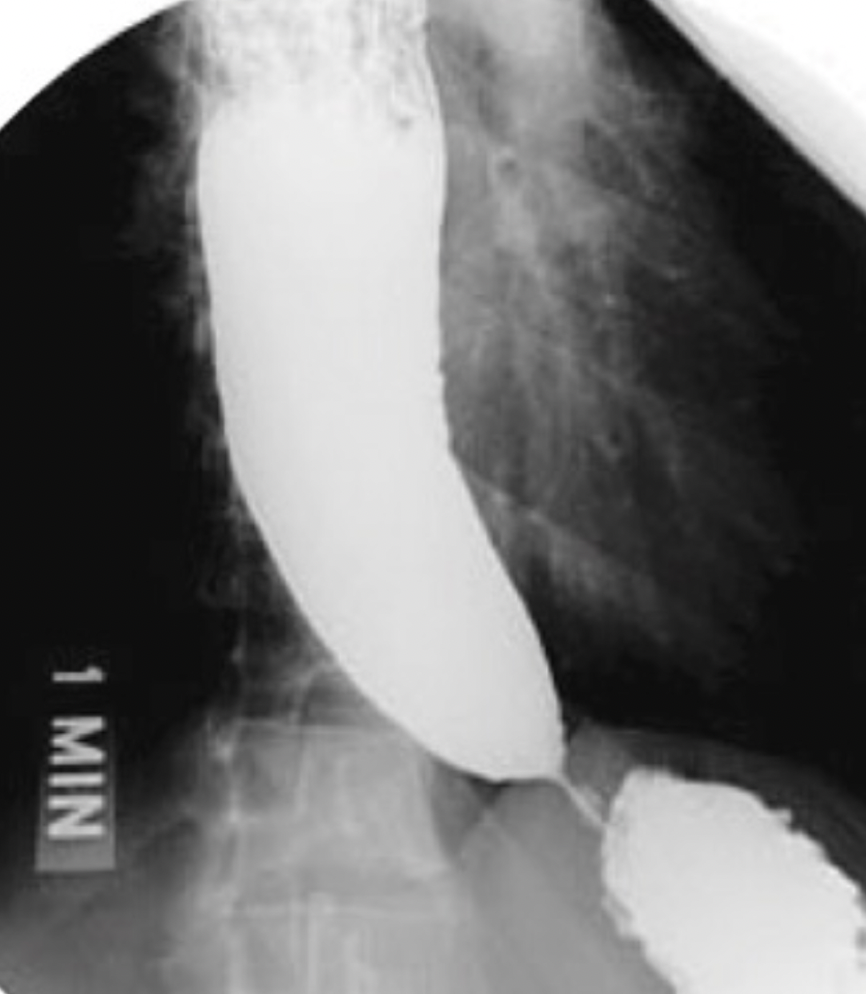

signo radiologico de acalasia

pico de pajaro